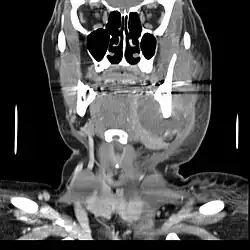

CT scan showing a large tooth abscess (right in the image) with significant inflammation of fatty tissue under the skin

If left untreated, a severe tooth abscess may become large enough to perforate bone and extend into the soft tissue eventually becoming osteomyelitis and cellulitis respectively. From there it follows the path of least resistance and may spread either internally or externally. The path of the infection is influenced by such things as the location of the infected tooth and the thickness of the bone, muscle and fascia attachments.